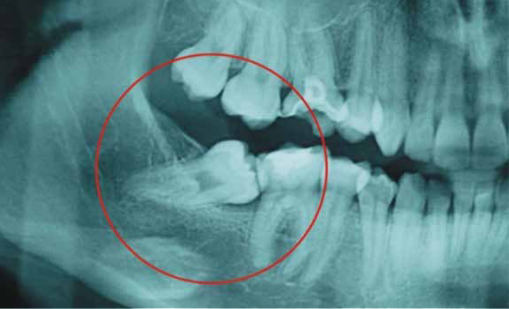

Extracciòn y cirugías